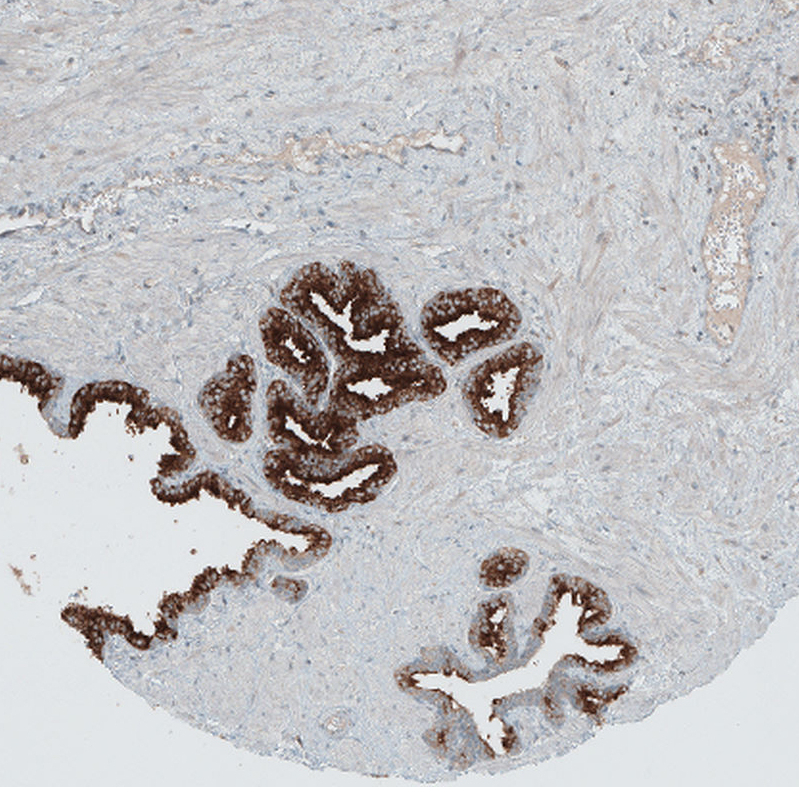

Immunohistochemical staining of human prostate shows moderate to strong cytoplasmic positivity in glandular cells.